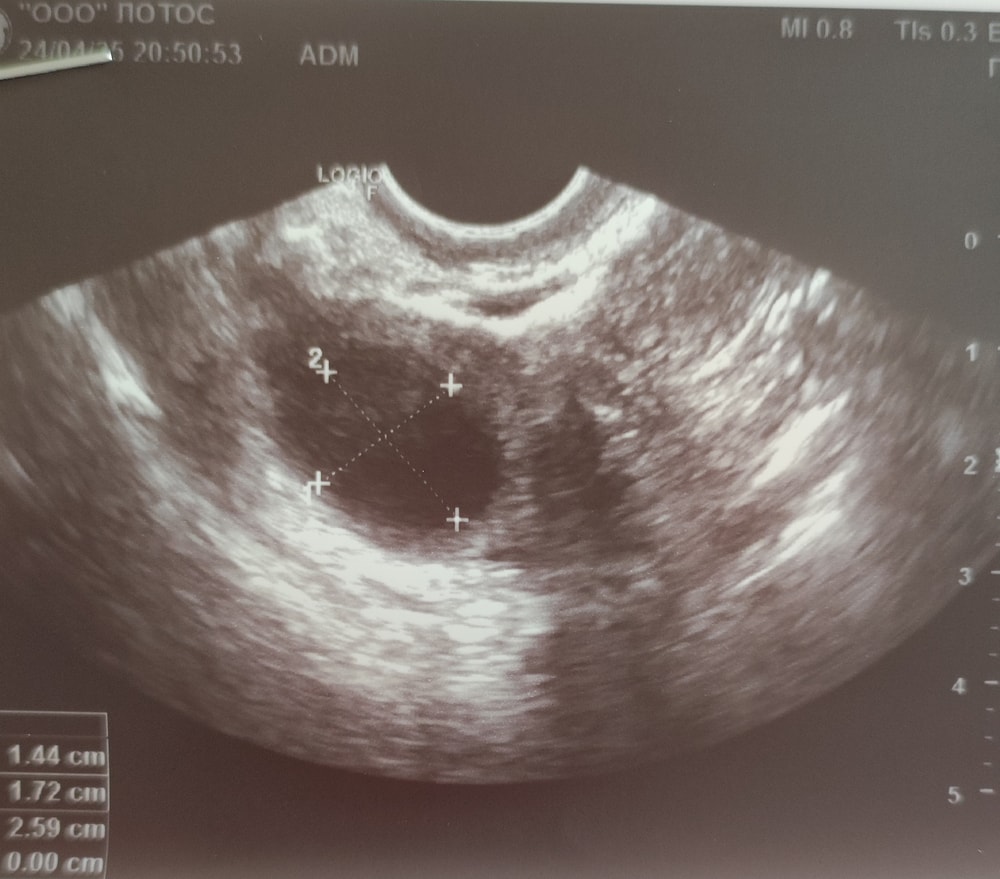

Фолликул или жёлтое тело?

Фолликул скорее всего. У жёлтого тела обычно края не такие ровные. Да и кровоток обнаружили бы у жёлтого тела, грамотный врач с фолликулом не перепутает.

Ох я видимо не знаток, но у меня так киста желтого тела выглядит🤔

Это фолликул)Дф еще Если б была жт то она как звездочка будет,совсем не круглая …

Последствия функциональной кисты Какой дпо?Когда была Овуляция??